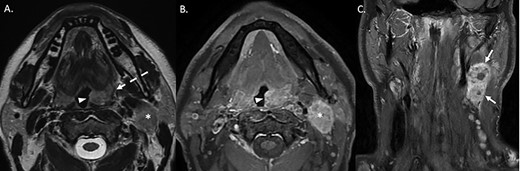

The patient underwent ultrasound-guided biopsy [7], revealing a metastatic lymph node: human papilloma virus (HPV)-positive and p16-positive squamous cell carcinoma (SCC). MRI neck showed soft tissue thickening within the left glossotonsillar sulcus, extending to the tongue base, and bulky, partially necrotic lymphadenopathy (Fig. 2). Panendoscopy and biopsy of the left tonsil showed non-keratinizing, HPV-associated SCC.

(A) T2-weighted axial sequence through the oropharynx, demonstrating asymmetric, exophytic enlargement of the left palatine tonsil (arrowhead). The signal within the middle constrictor is preserved (dashed arrow). An enlarged level II lymph nodal lesion is also noted (asterisk). (B) Axial post-gadolinium fat-suppressed sequence at the same anatomical level demonstrates heterogeneous enhancement of the enlarged let palatine tonsil (arrowhead). The ipsilateral level 2 nodal lesion is also noted (asterisk). (C) Coronal post-gadolinium fat-suppressed sequence demonstrates a conglomerate nodal mass at level 2–3 on the left with areas of central non-enhancement compatible with necrosis.